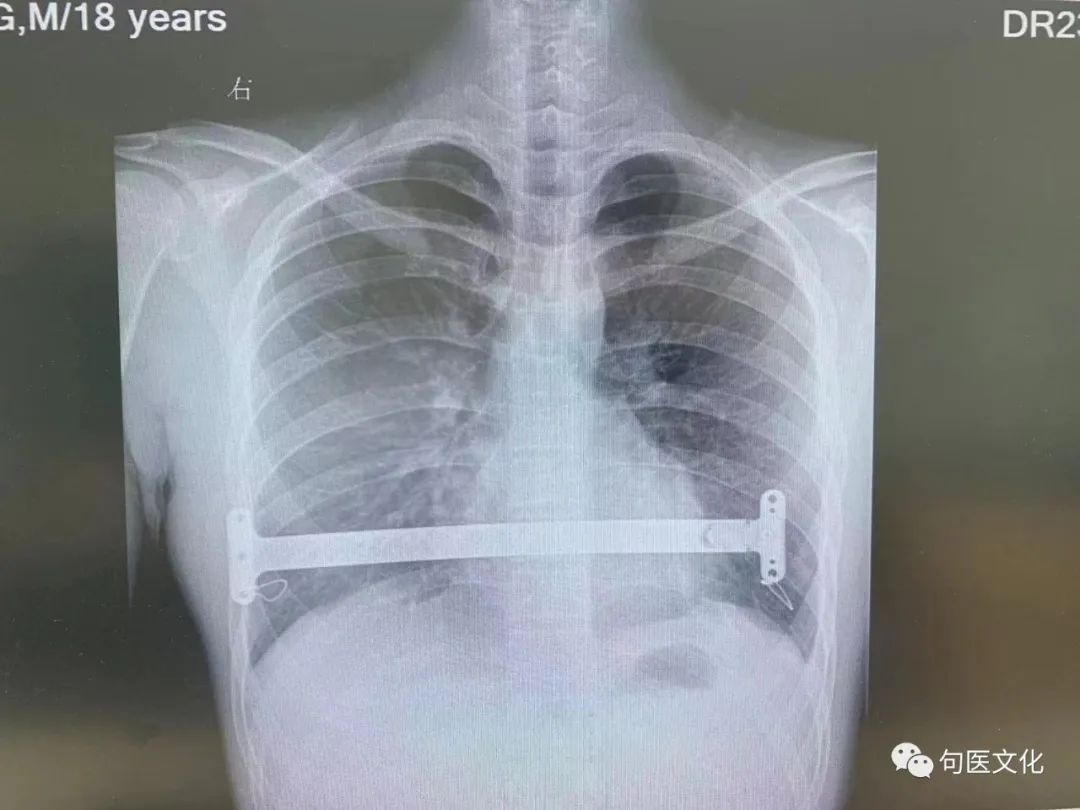

近日,18 岁的男孩小朱在父母的陪同下,来到我院胸外科就诊。小朱自幼胸前区有点凹陷,近些年有加重,影响身心健康。胸外科张金明副主任医师查体发现小朱前胸壁凹陷畸形,呈漏斗状,最低点位于胸骨体中下部,初步诊断为「漏斗胸」。

手术方式为目前国际上先进的胸腔镜下漏斗胸超微创矫形技术,这种新型手术方式与传统方式相比较,具有手术切口小、创伤小、愈合快、住院时间短等优势。

手术由上级医院专家及本院张金明副主任医师,葛明帅主治医师共同施行。由于术前准备充分,手术进展非常顺利,历时仅一个小时,全程没有切除任何肋骨,没有切开胸大肌,

仅在左右腋下分别打开约 3 厘米的切口。术后小朱恢复快,第 2 天就能下床活动,胸廓基本恢复正常形状,矫形效果满意。